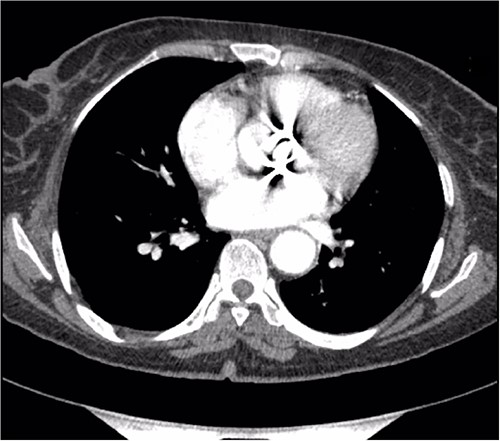

A thorough cardiovascular examination was performed, which revealed normal prosthetic valve clicks and a grade 3 ejection systolic murmur in the right second parasternal space. Further investigations included a transesophageal echocardiogram (TEE), which showed a paravalular anechoic free space around the prosthetic mechanical aortic valve with paravalular leakage and regurgitant flow with dehiscence of the prosthesis causing aortic stenosis (Fig. 1). A computed tomography (CT) scan was also performed to rule out aortic calcification, which revealed a normally seated aortic valve prosthesis with no visualization of the paravalular free space (Fig. 2). During the preoperative workup, blood cultures showed bacterial growth of Brucella melitensis. A multidisciplinary team approach was initiated, and the patient was started on antimicrobial therapy with gentamicin, doxycycline and rifampin. However, due to the patient developing abnormally high levels of Aspartate aminotransferase (AST) and Alanine aminotransferase (ALT), which is a side effect of rifampin, the regimen was changed to ceftriaxone, doxycycline and trimethoprim/sulfamethoxazole.

Preoperative TEE: (A) Red arrow pointing at a paravalvular anechoic free space around the prosthetic mechanical aortic valve. (B) Echo image showing paravalvular regurgitation and leakage around the prosthetic mechanical valve. (C) 3D reconstructive echocardiography image showing paravalvular free space around the aortic mechanical valve at 3–9 o’clock with aneurysmal echo free space at the aortomitral curtain protruding into left atrium. (D) Aortic prosthetic mechanical valve dehiscence causing aortic stenosis with moderate paravalvular regurgitation.